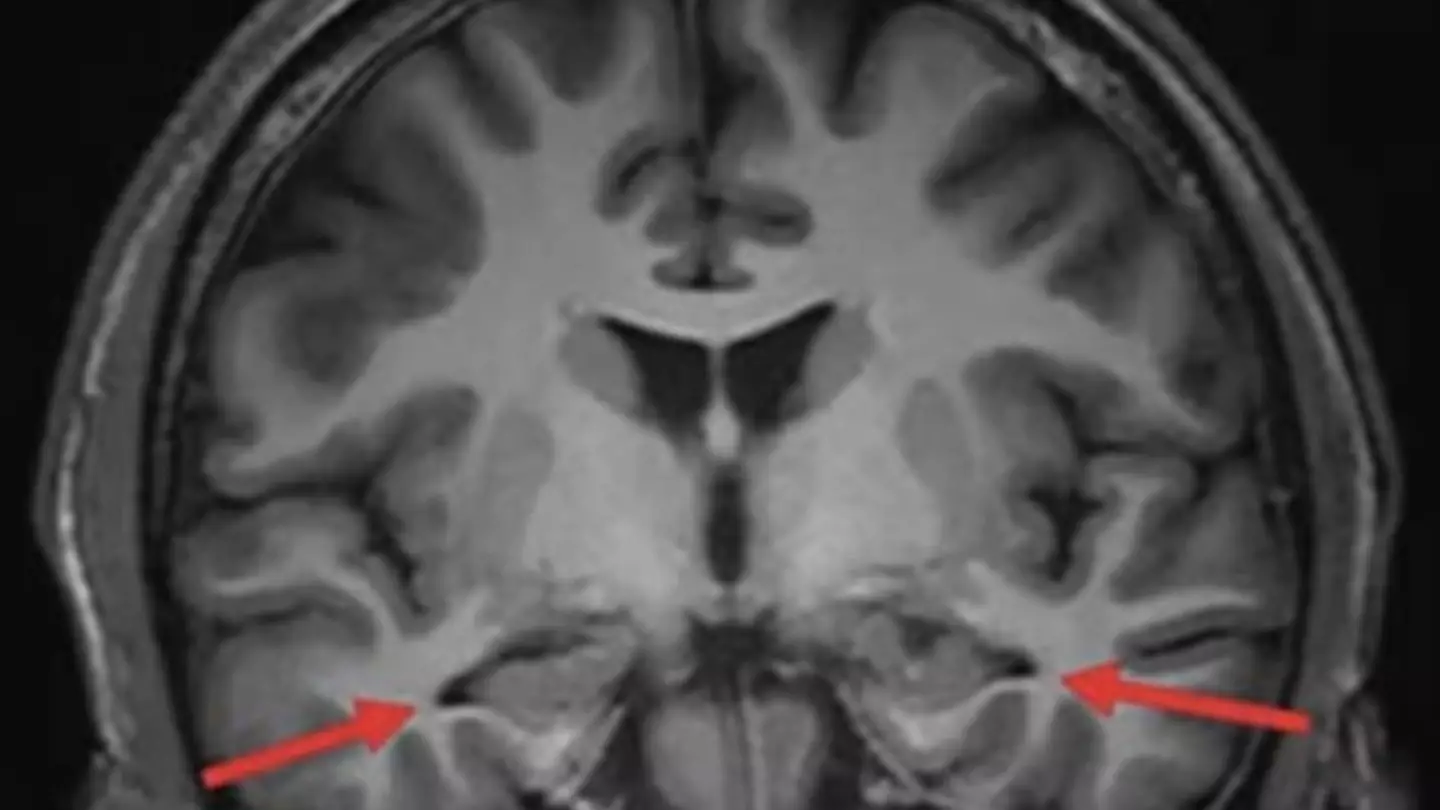

Brain scan of 'youngest ever' Alzheimer's patient shows devastating impact of disease

The teenager, from Beijing, first began experiencing symptoms when he was still in school